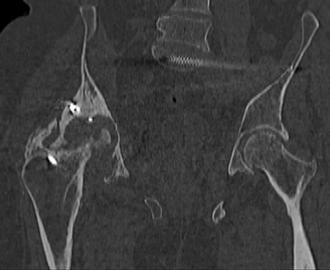

Пациент 49 лет, паровозная травма 23.2.2006, получил вертикальная нестабильное повреждение таза, разрыв левого крестцово-подвздошного сочленения, перелом лонной, седалищной костей слева, T-образный оскольчатый перелом правой вертлужной впадины с переломом заднего края, вывих правого бедра, посттравматическая пояснично-крестцовая плексопатия с обеих сторон, паралич мышц правой голени. В день травмы - вправление вывиха, скелетное вытяжение, 14.3.2006 чрескостный остеосинтез таза. 20.4.2006 остеосинтез правой вертлужной впадины пластинами, осложнившийся нагноением межмышечной гематомы правой ягодичной области. Получал консервативное лечение, было достигнуто полное заживление раны. 24.7.2006 введены илиосакральные винты слева. С декабря 2006 года и по настоящее время ходит на костылях без опоры на правую ногу. Планируется THA. Помогите определиться с вариантом костной пластики? И какую укрепляющую конструкцию использовать?